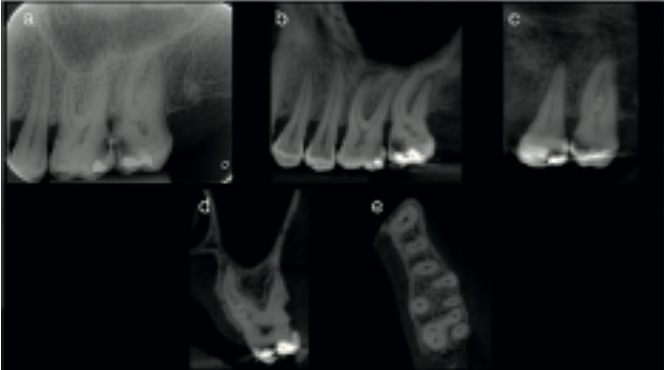

Fig. 5 — Pre-operative, post-operative, and two-year follow-up periapical radiographs showing successful treatment

Fig. 5 (a) Pre-operative periapical radiograph. (b–c) Final obturation films. (d) Two-year review confirming periapical health and no symptoms.

Post-operative radiographs showed satisfactory obturation of all identified canals. At two-year follow-up, the tooth remained asymptomatic with healthy periapical tissues — a successful outcome that would have been unlikely had the second palatal canal been missed.